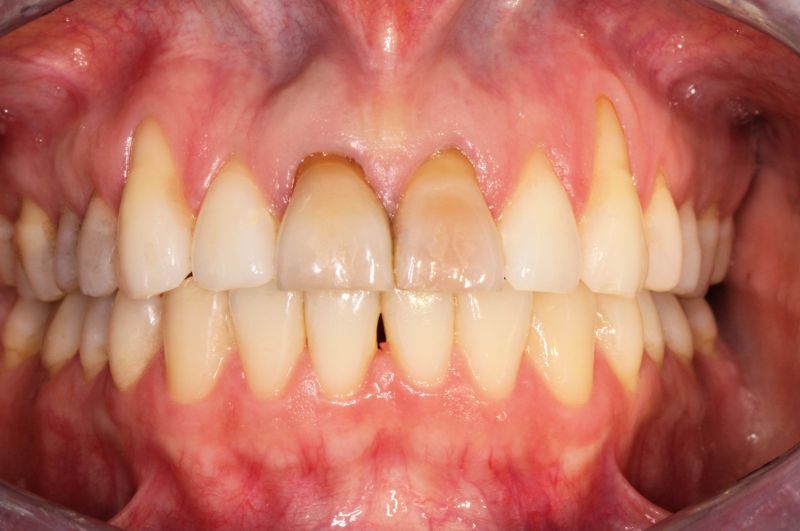

Odsłonięte szyjki zębowe - Przyczyny i sposoby leczenia

Odsłonięte szyjki zębowe to problem, który dotyczy wielu pacjentów, najczęściej w średnim wieku. Z pozoru temat może wydawać się błahym problemem, jednak nie należy lekceważyć tego stanu, gdyż może doprowadzić do poważnych zaburzeń w jamie ustnej. Specjalistą, do którego należy udać się z takim problemem, jest lekarz, który zajmuje się chorobami przyzębia, czyli periodontolog.